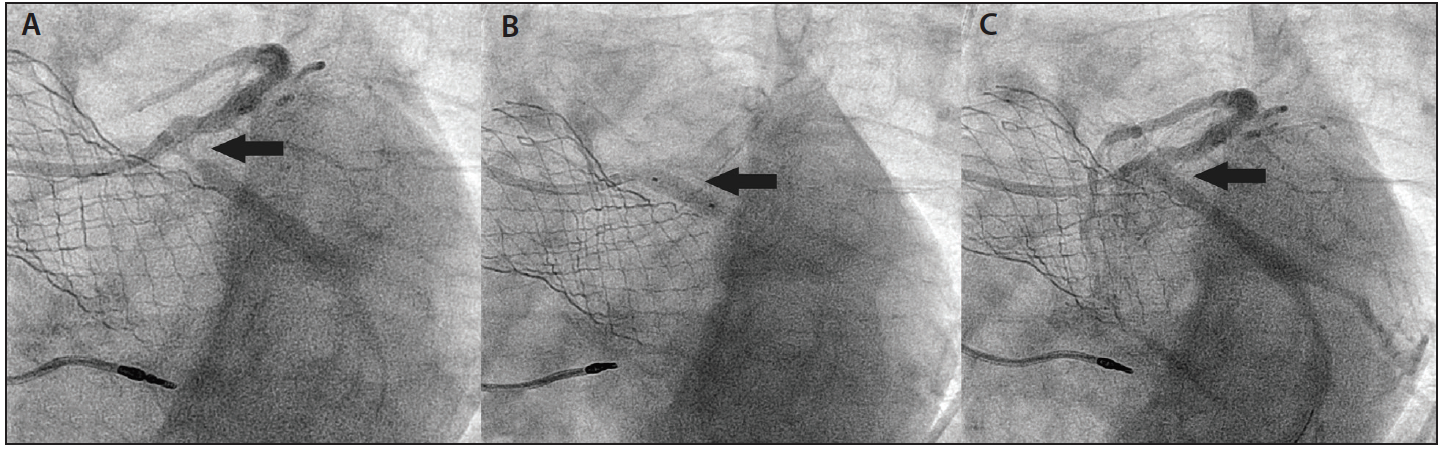

An additional consideration regarding the timing of PCI is the impact of TAVR on the anatomy of the aortic root. The TAVR valve frame and the displaced native aortic valve leaflets can obstruct the coronary ostia after implantation, rendering PCI after TAVR technically challenging. Other factors to consider include the type of TAVR device, depth of implantation, length of the native aortic valve leaflets, and location of the coronary artery ostia. Simply engaging the coronary ostia through the frame of a self-expanding TAVR device can be difficult, if not impossible. Figure 2 illustrates a case we recently encountered. An 88-year-old man presented with non-ST elevation myocardial infarction, 9 months after TAVR with a self-expanding device. A nuclear stress test yielded positive findings, with inducible ischemia in the lateral wall. Selective coronary angiography was performed through the open cells of the TAVR device using a 6-F, Judkins left 4 guide catheter. De novo focal stenosis in the proximal left circumflex artery was identified and treated with deployment of a drug-eluting stent (DES). If timing, renal function, and clinical presentation permit, we have found that contrast-enhanced cardiac computed tomography can be very useful to identify the relationship of the TAVR valve frame, the displaced native aortic valve leaflets, and the coronary ostia to plan the PCI. If PCI is deferred before TAVR, but is believed to be likely required in the future, a shorter balloon-expandable TAVR device may be preferable to a self-expanding device to facilitate subsequent access to the coronaries.

Figure 2. Percutaneous coronary intervention of the left anterior descending artery 9 months after transcatheter aortic valve replacement (TAVR) with a self-expanding CoreValve system (Medtronic). A 6-F Judkins left 4 guide engaged in the left main ostium through the cells of the self-expanding TAVR device. Arrow indicates a stenosis in the proximal left circumflex (A). After predilatation with a 3-mm balloon, a 4-mm X 12-mm DES was successfully deployed (B; arrow). The final angiographic result showed no residual stenosis (C; arrow).